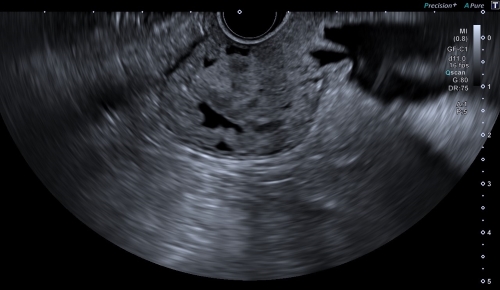

An EUS visualization benefit is inherent in the differentiation in shading it provides with the ultrasound image. D-THI (Differential Tissue Harmonic Imaging), developed by Canon Medical, enables high-resolution images with high resolution from near to far field. This expects rapid identification of tumors, cysts, and other lesions from normal tissue, supporting diagnosis and treatment. “With D-THI, endoscopists are assisted in identifying each of the five layers of the gastrointestinal wall with high contrast”, says Dr. Rodica Gincul from the Jean Mermoz Private Hospital – Ramsay Health in Lyon, France, while her colleague Dr. Bertrand Napoléon emphasizes: “The higher resolution imaging of Aplio at greater depth through the use of D-THI allows me to safely visualize and reach bile ducts even at very deep locations, improving therapeutic biliary drainage and patient care.

D-THI